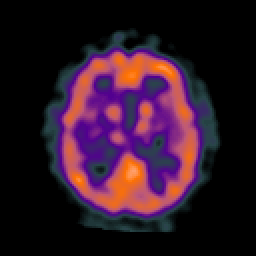

AIDS dementia: overlay -- Slice #11

[Home][Help][Clinical][Tour 1] Slice 11